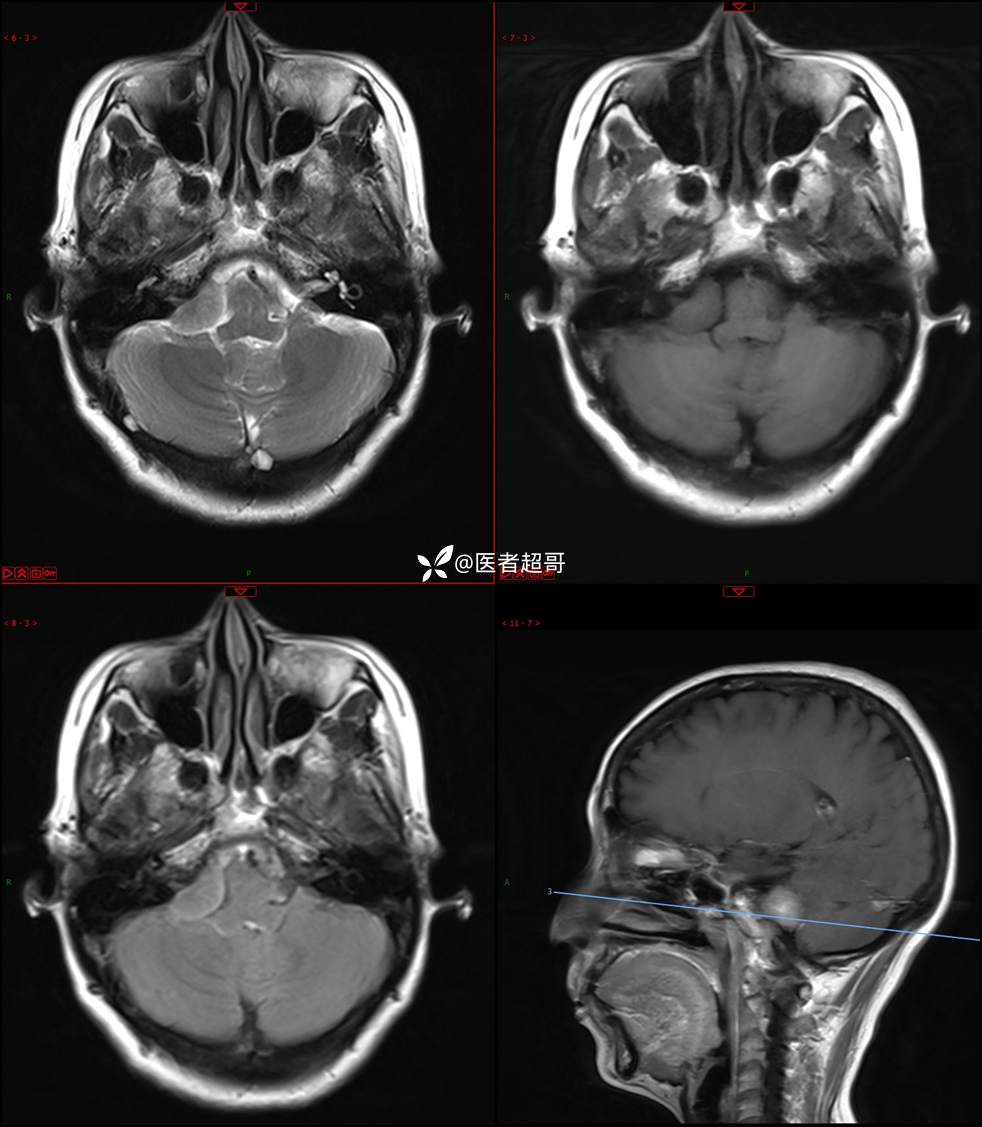

CPA区占位,是鞘瘤?脑膜瘤?请赏析!

主 诉:耳鸣3年,头晕伴恶心4天。

现病史:患者3年前出现耳鸣,蝉鸣音,反复发作,夜间自觉明显,于2018年8月至我院耳鼻喉科就诊,行颅脑CT检查未发现明显异常改变,给予对症处理(具体不详);4天前突发头晕,伴明显恶心,至市人民医院就诊,行颅脑CT未见明显异常,颅脑MRI发现右侧桥脑小脑角区占位性病变。本次发病来无明显头痛,无肢体抽动,无大小便失禁。为求进一步诊治,遂来我院门诊,以“听神经良性肿瘤”收住入院。发病来,患者神志清,精神可,二便正常,饮食可,睡眠不佳,近期体重无明显变化,否认癫痫发作病史。